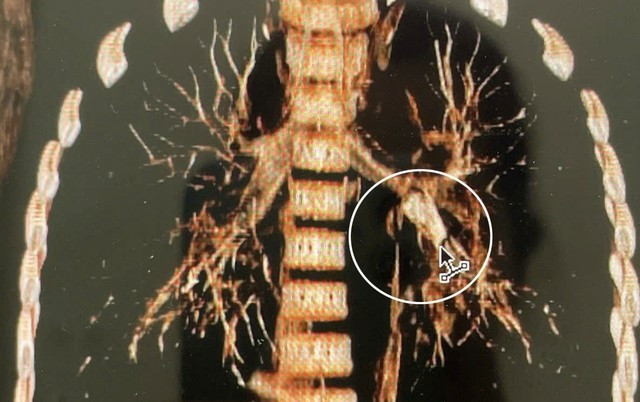

Qua thăm khám lâm sàng, các bác sĩ nghi ngờ trẻ bị hóc dị vật đường hô hấp. Kết quả chụp CT ngực ghi nhận dị vật hình ống, thành dày khoảng 1,8 mm, dài khoảng 18 mm, nằm tại phế quản thùy dưới trái, gây cản trở thông khí.

Dị vật nằm tại phế quản thùy dưới bên trái. Nguồn SKĐS